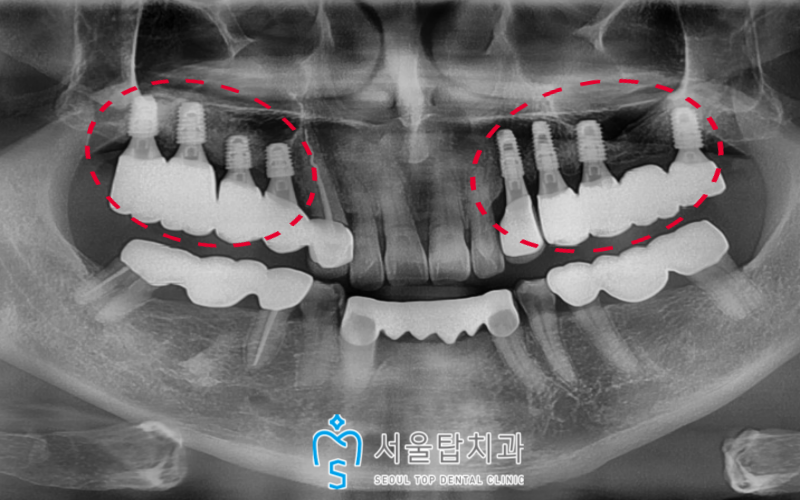

왼쪽에 부러진 치아를 2개 발치하고

기존 상실된 부위와 함께

임플란트 식립을 진행한 모습입니다.

오른쪽은 작은 어금니 자리(#14, 15)는

바로 식립을 진행하였으며

큰 어금니 부분은

상악동 거상술과 뼈이식을 진행하였고,

기반이 갖추어지고 난 이후

임플란트를 식립 할 예정입니다.

(환자분의 경우 6개월 후)

오른쪽 작은 어금니 자리 또한 (#14,15)

인공치근인 픽스처가

잇몸뼈에 단단하게 고정 된 것을 확인한 후

보철작업을 도와드렸습니다!

더불어 약 6개월이 지난 후

상악동 거상술 + 뼈이식을 진행하였던

큰 어금니 자리(#16,17)는

이제 임플란트를 식립할 수 있는

충분한 기반이 갖추어져

식립을 도와드렸답니다.

오른쪽 어금니 자리도 인공치근이

뼈에 잘 유착된 것을 확인한 후

보철 과정까지 마무리 해드렸습니다.

양측 모두 임플란트 치료를

성공적으로 마무리 해드린 모습입니다!

🦷 치료후 🦷